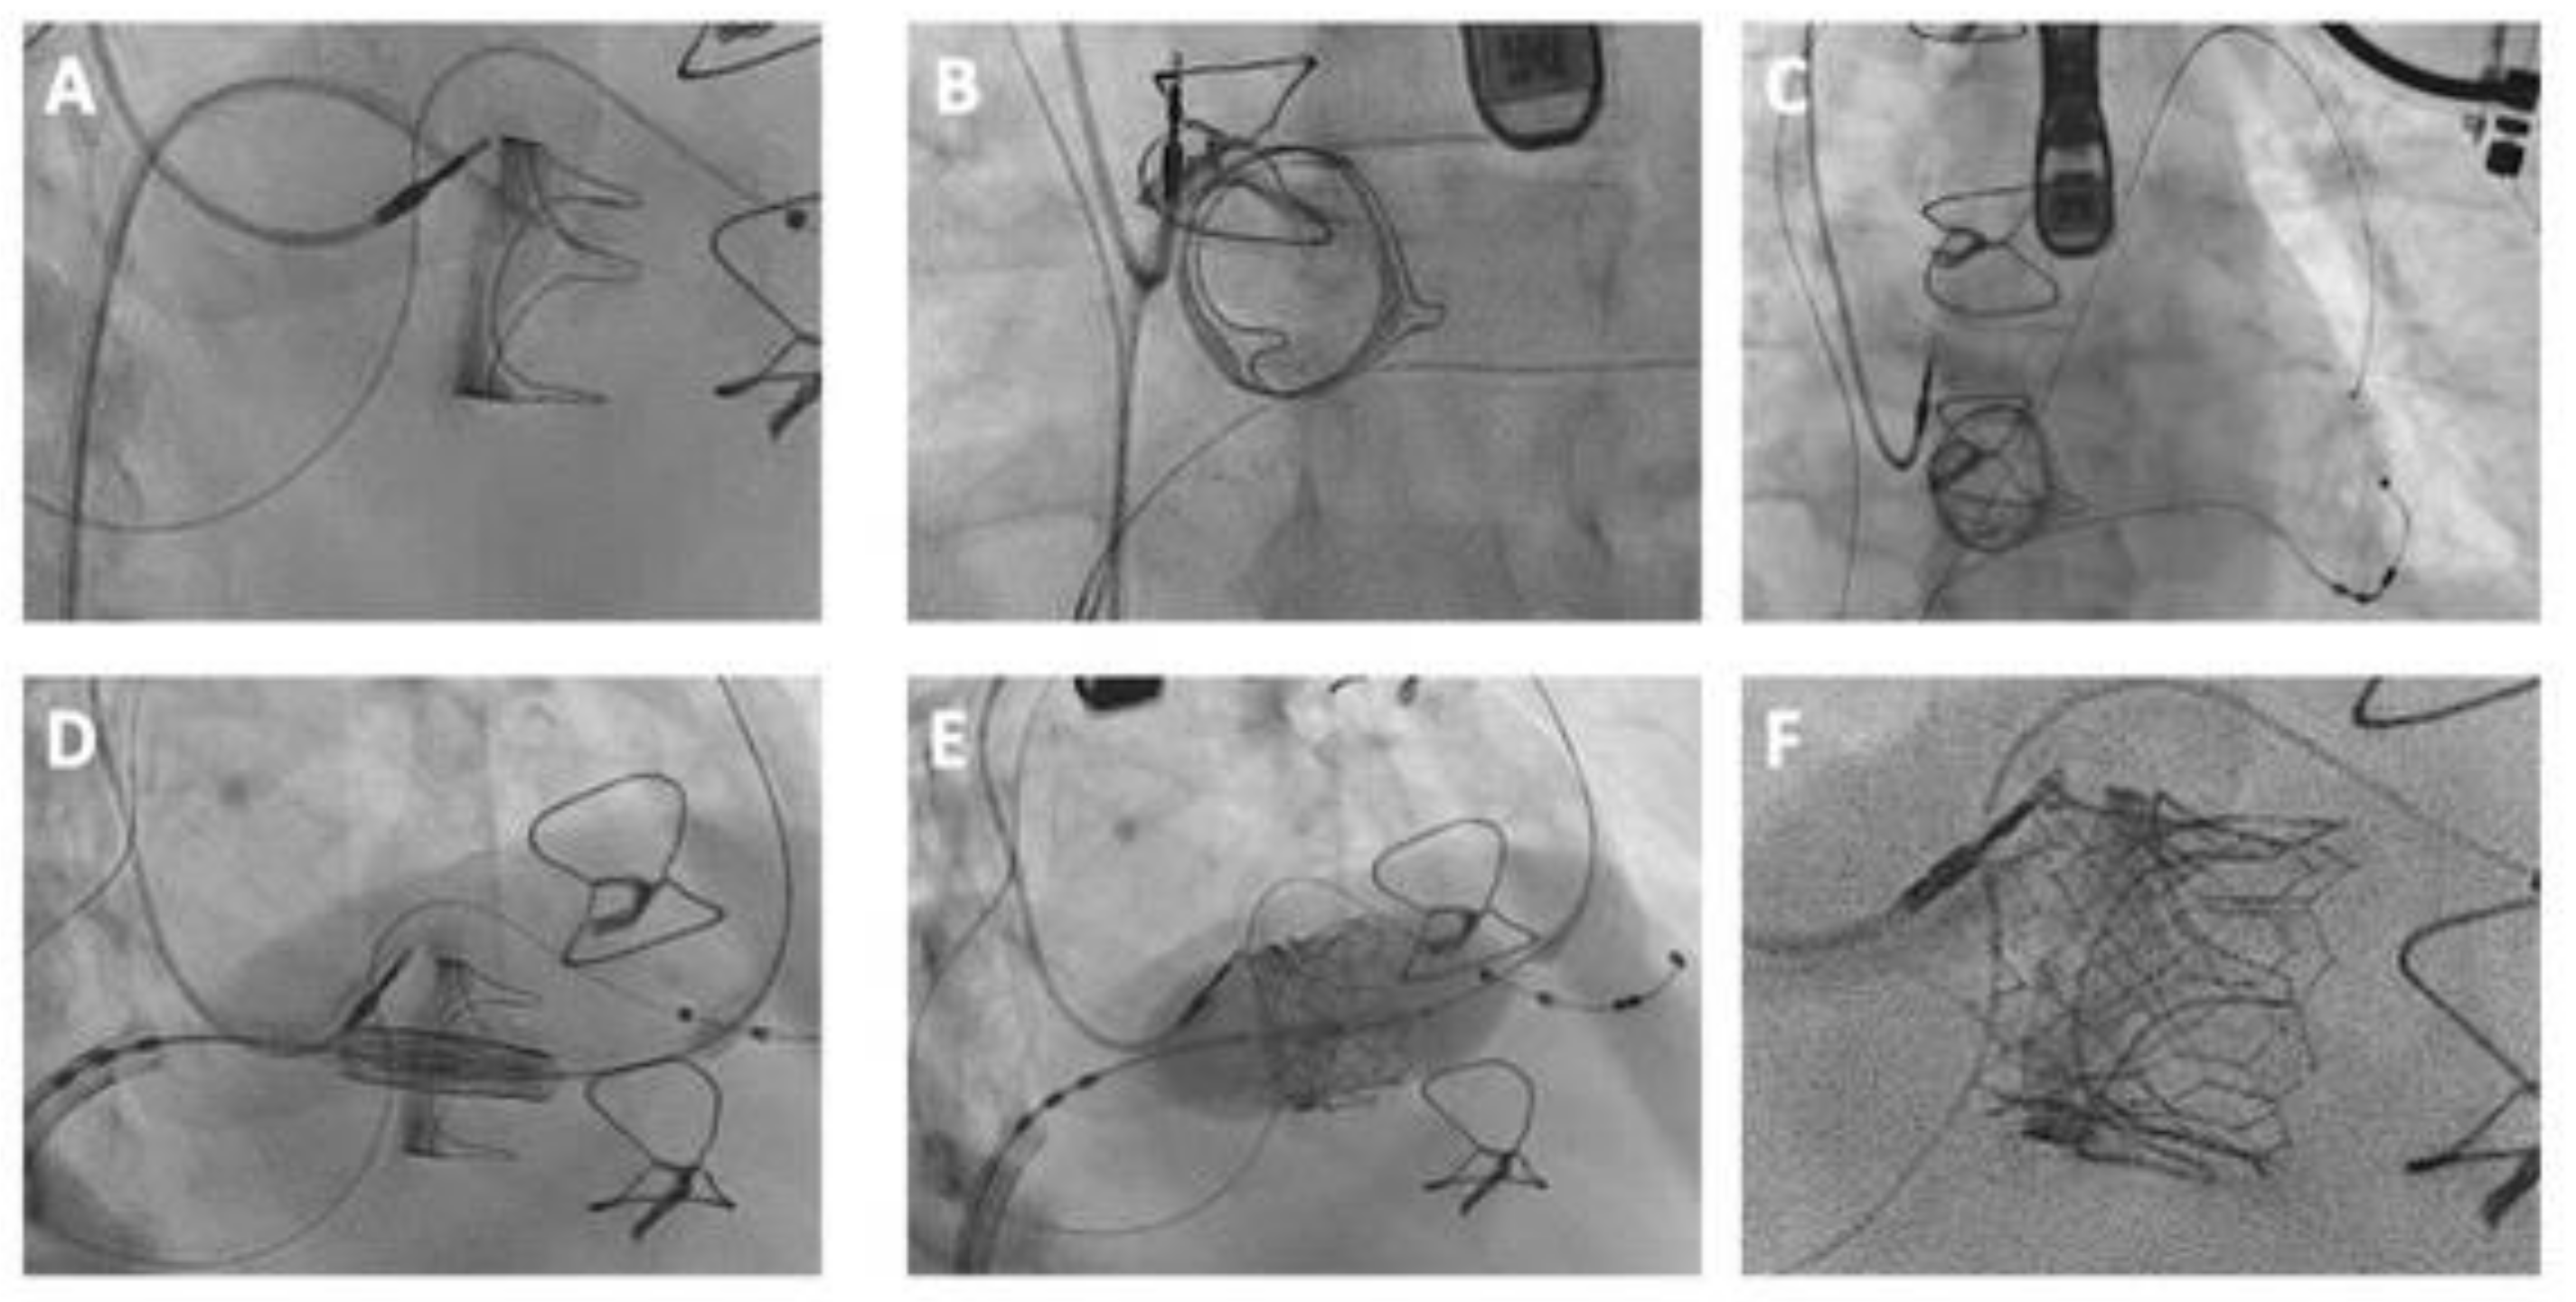

5.3.2. Crossing the Tricuspid Valve

Navigating the tricuspid valve can be challenging, especially with a small valve orifice or severely dilated right atrium. Adjusting fluoroscopy helps provide an optimal view of the prosthesis, facilitating catheter guidance (Figure 6). Employing a multipurpose catheter with a shaped wire aids in directing the catheter toward the tricuspid valve. Additionally, using a steerable sheath in combination with an angled wire ensures a secure catheter position during guidewire deployment into the right ventricular apex [73,94,95].

5.3.3. Wire Positioning

Upon successful traversal of the tricuspid valve, the wire is most commonly positioned in the pulmonary artery for extra support, but right ventricular apical positioning is also possible (Figure 6).